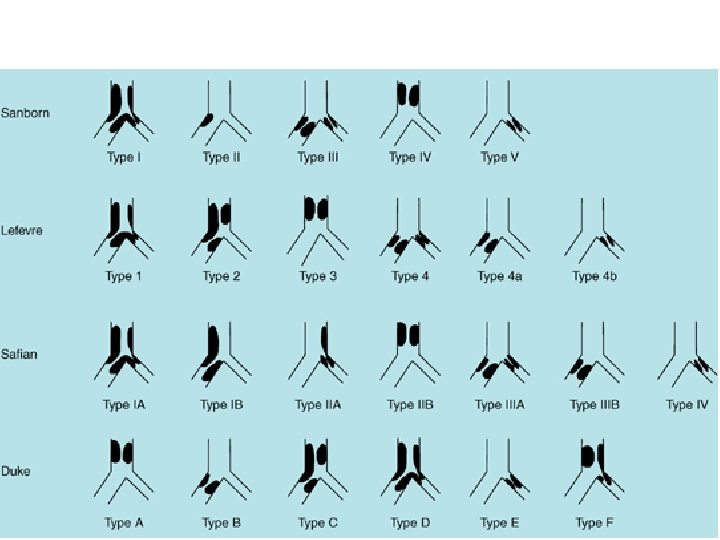

Classification • • Sanborn Lefevre Safian Duke • MEDINA • MOVAHED